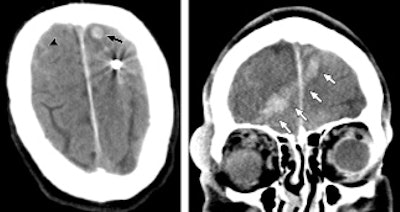

CT images of a 65-year-old man who sustained penetrating neurologic trauma from a ball bearing. Noncontrast CT (left) reveals a spherical metallic density lodged in the left frontal lobe with subarachnoid (arrowhead) and intraparenchymal hemorrhage (arrow). Coronal reformation (right) shows intracranial hemorrhage along the ball bearing's path from the right orbit through the right frontal lobe to the left frontal lobe (arrows). Images courtesy of Radiology.Among the findings in the BWH review was a slowdown in x-ray completion time. The problem was not in image acquisition, but rather in having to route the images through the facility's lone single-plate x-ray reader. The bottleneck lengthened x-ray completion time to 52 minutes, up from 31 minutes under routine emergency x-ray conditions.